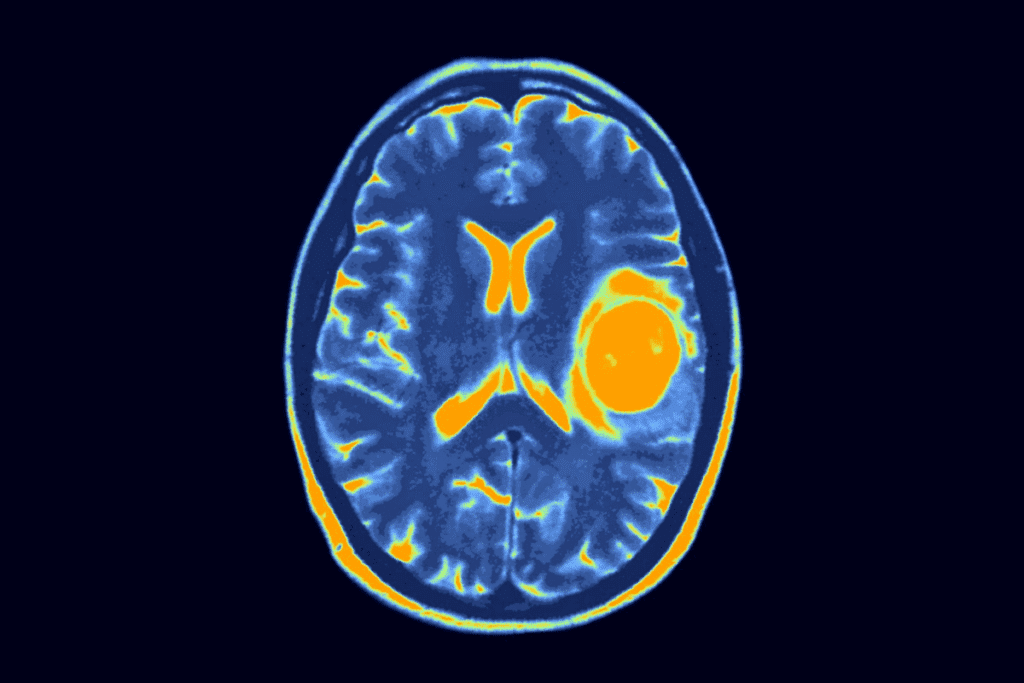

To diagnose neuroblastoma, doctors use imaging like ultrasound and CT scans, along with a biopsy. The diagnosis of neuroblastoma is key to figuring out the stage and risk. This helps decide the best treatment.

Familiarity with the fundamentals of neuroblastoma aids in comprehending its complexities and potential outcomes.